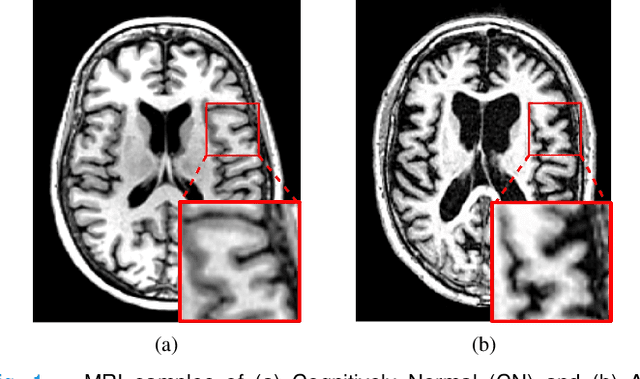

Abstract:Early diagnosis of Alzheimer's disease and its prodromal stage, also known as mild cognitive impairment (MCI), is critical since some patients with progressive MCI will develop the disease. We propose a multi-stream deep convolutional neural network fed with patch-based imaging data to classify stable MCI and progressive MCI. First, we compare MRI images of Alzheimer's disease with cognitively normal subjects to identify distinct anatomical landmarks using a multivariate statistical test. These landmarks are then used to extract patches that are fed into the proposed multi-stream convolutional neural network to classify MRI images. Next, we train the architecture in a separate scenario using samples from Alzheimer's disease images, which are anatomically similar to the progressive MCI ones and cognitively normal images to compensate for the lack of progressive MCI training data. Finally, we transfer the trained model weights to the proposed architecture in order to fine-tune the model using progressive MCI and stable MCI data. Experimental results on the ADNI-1 dataset indicate that our method outperforms existing methods for MCI classification, with an F1-score of 85.96%.